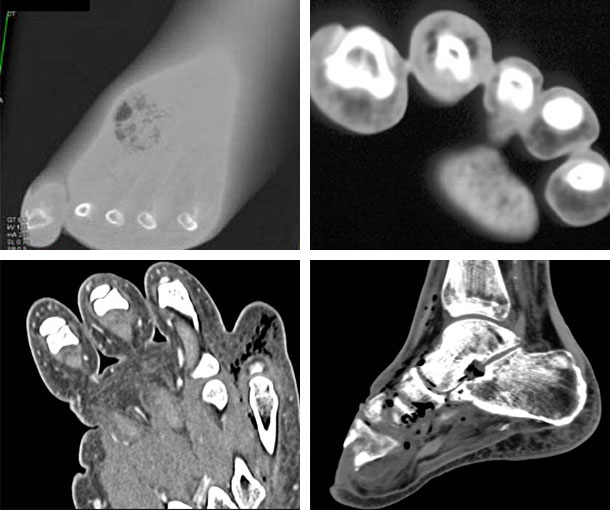

Gas Gangrene CT Findings

- Myonecrosis with reduced enhancement

- Asymmetrical fascial thickening

- Subcutaneous emphysema

- Fat stranding

- Fluid collection

- Formation of abscesses

- May be associated with osteomyelitis